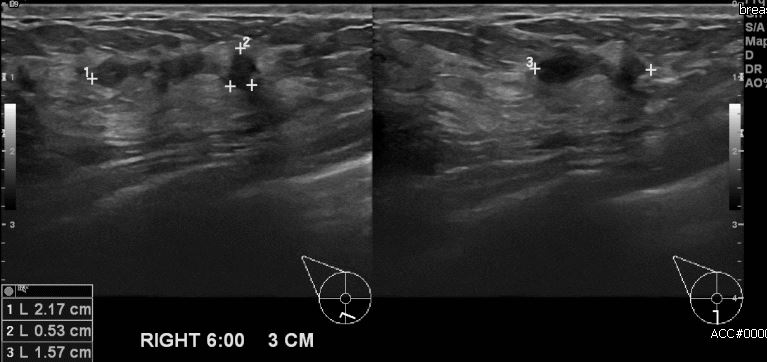

건강 검진상 이상 소견으로 내원하신 40대 여성 분으로  우측 6시 방향에 3cm

거리의 의심스러운  혹 조직검사 시행하여 우측 침윤성 유관암 진단 되었습니다.